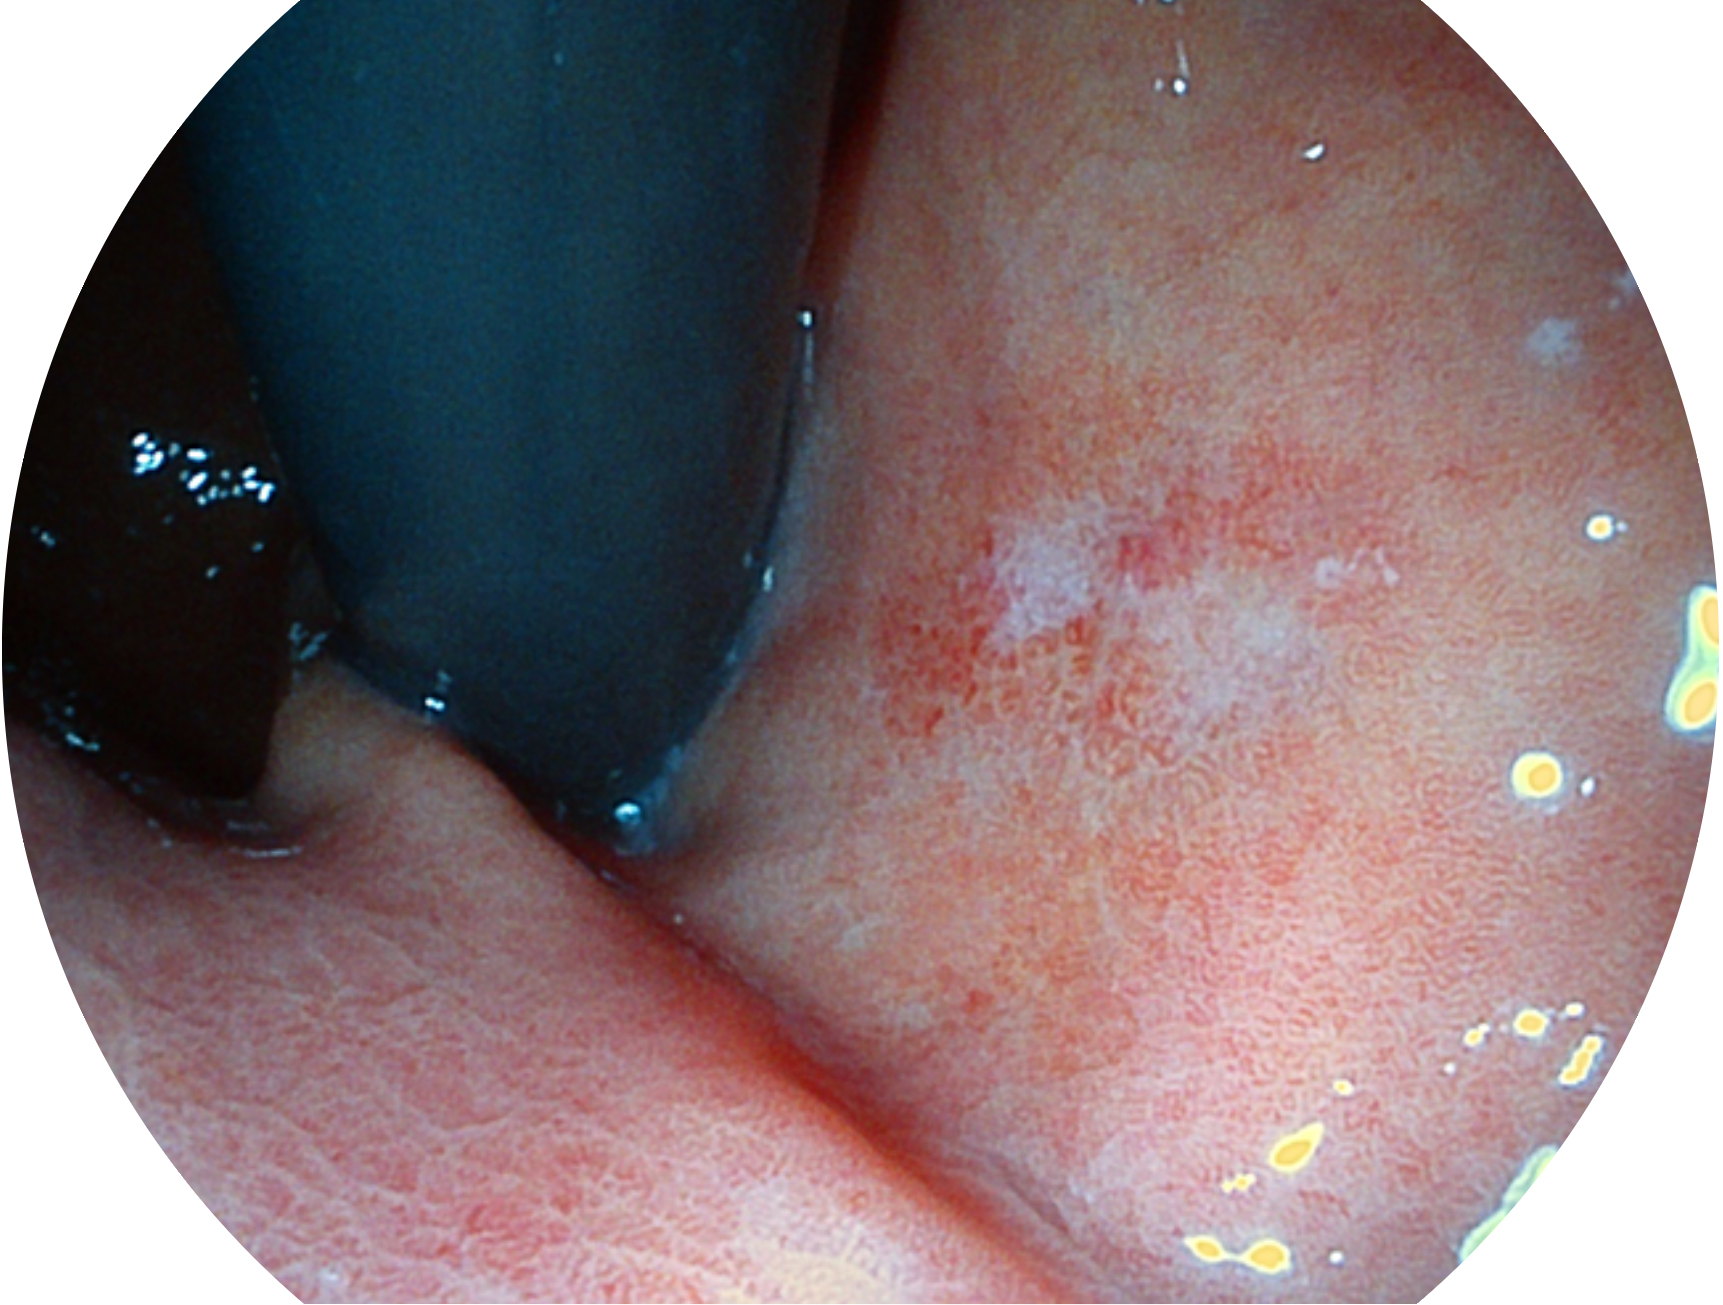

1xBET新开发的内镜染色技术,主要是基于多波长LED 光源的开发,VLS-55Q 四波长LED 光源是由四个不同颜色的LED光按照相应照明模式所规定的特定发光比例进行合束后形成,合束后形成的照明光的光谱由红光、绿光、蓝光及蓝紫光这四个不同的波段范围构成。具有更高光谱自由度,通过光谱比例的控制,实现了聚谱成像技术,英文全称为“Spectral Focused Imaging, SFI”,缩写为“SFI”和光电复合染色成像技术,英文全称为“Versatile Intelligent Staining Technology, VIST”,缩写为“VIST”。